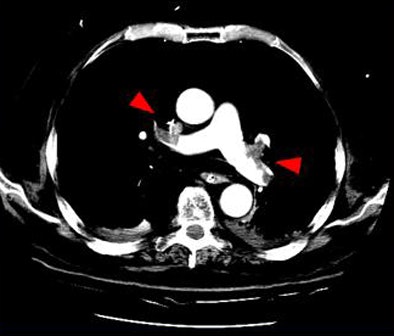

| Above, small filling defects, or dots, may represent normal embolic activity originating from the lower-extremity venous valve cusps. Below, location of dots in 27 of 101 patients diagnosed with PE in the study population. |

| Dots not clots: Above, thoracic CT angiogram of a 36-year-old woman with chronic myeloid leukemia (CML) and graft-versus-host disease (GVHD) who presented with fever and chest pain. Diagnosed with PE, the report noted 1-mm emboli in the segmental and subsegmental branches of the right lower lobe pulmonary artery. Below, in a 59-year-old man presenting with dyspnea and chest pain, CT angiography detected two 2-mm clots in the peripheral subsegmental branches of the lower lobes. |